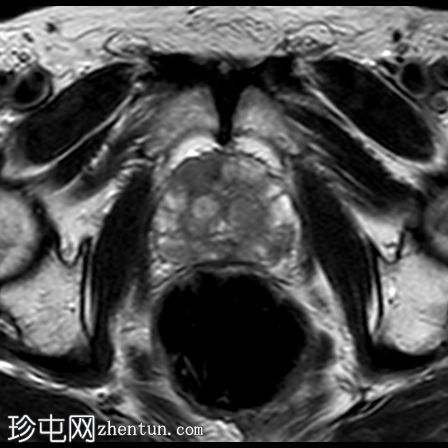

轴位

T2加权像

右侧前列腺前中带可见一边界不清的18 x 10 mm扁豆状病灶,T2加权像呈低信号,扩散受限(DWI高信号,ADC低信号),与周围实质相比早期强化,病灶位于前移行区与纤维肌性间质交界处。影像学表现符合PI-RADS 5级病灶。

未见前列腺外侵犯、盆腔淋巴结肿大或疑似骨病变。

T2加权像显示骶骨翼骨髓高信号,T2/STIR序列抑制,提示脂肪骨髓沉积。